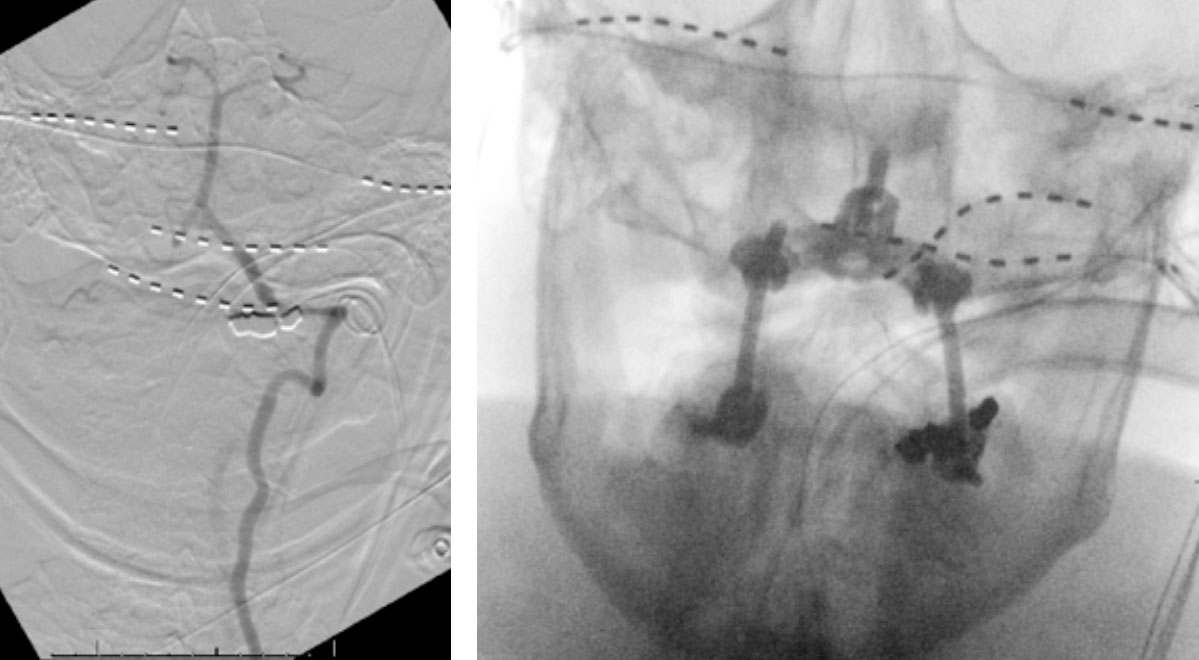

Dynamic provocative fluoroscopy failed to reveal significant Vertebral osseous instability (Figure 2A), however, Transcranial Doppler Flow velocities in the distal right Vertebral and Basilar Artery are markedly reduced during Extension of the Neck (Figure 2B).